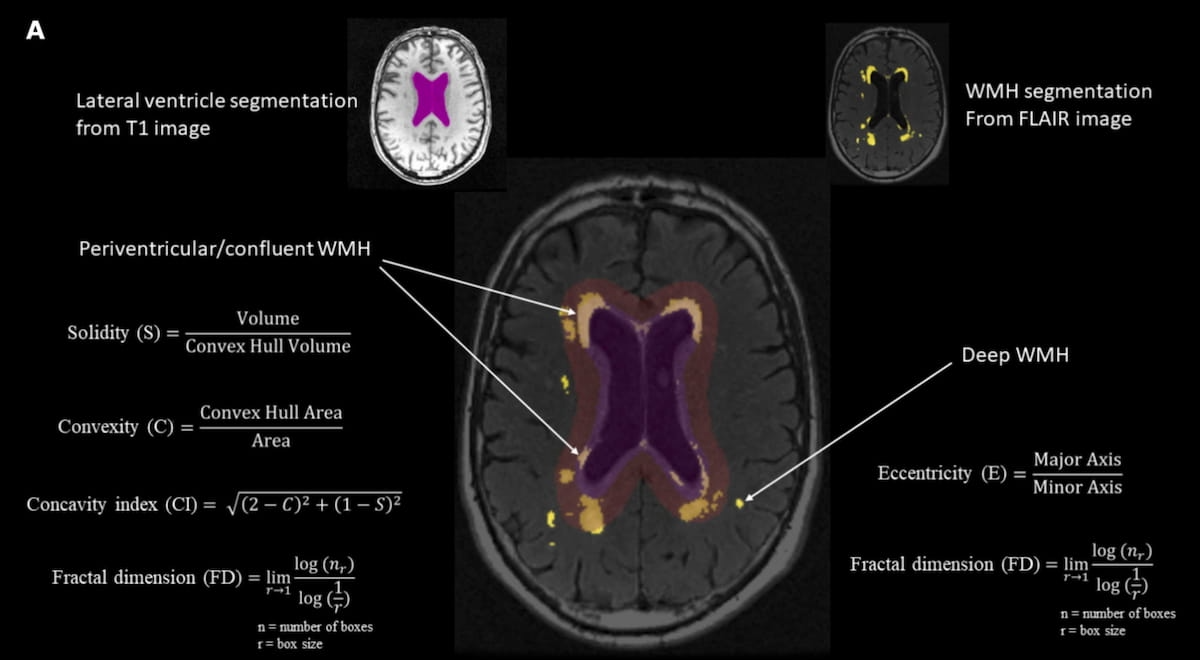

Here can see a graphic showing the calculation of white matter hyperintensity shape makers derived from brain MRI scans. New research suggests that irregular shape of the periventricular/confluent white matter hyperintensity is associated with cognitive decline in the executive function, memory, and processing speed domains over a five-year period. (Graphic courtesy of Neurobiology of Aging.)

For associations with cognitive decline in the memory domain, the study authors noted a higher fractal dimension (-0.07) and concavity index (-0.09) as well as lower convexity (-0.07) and lower solidity (-0.04) with periventricular/confluent WMH shape irregularity.

For cognitive decline with executive function, the researchers pointed out irregularity in periventricular/confluent WMH shape in the form of lower convexity (-0.04) as well as higher fractal impression (-0.04) and concavity index (-0.04). The study authors said those patients with cognitive decline in processing speed had lower solidity (-0.04) and convexity (-0.06) along with higher fractal dimension (-0.06) and concavity index (-0.08) with the irregular shape of periventricular WMH.

1. WMH shape may help predicts cognitive decline. Irregular shapes of periventricular/confluent white matter hyperintensities (WMHs) on brain MRI are significantly associated with decline in executive function, memory, and processing speed over a 5.2-year period independent of WMH volume.

2. Specific shape markers matter with periventricular/confluent WMH. Cognitive decline appears to be correlated with specific WMH shape features, such as higher fractal dimension and concavity index, and lower convexity, suggesting these metrics may be useful in early identification of at-risk individuals.

3. Periventricular vs. deep WMH. While the shape of periventricular/confluent WMHs was linked to cognitive decline. the study authors found no significant association with deep WMH shape. The researchers added that more extensive changes in the regions of long associating fibers with subcortical nuclei and other more distant brain regions "may have more severe consequences" in contrast to the punctual changes one may detect in deep white matter regions.